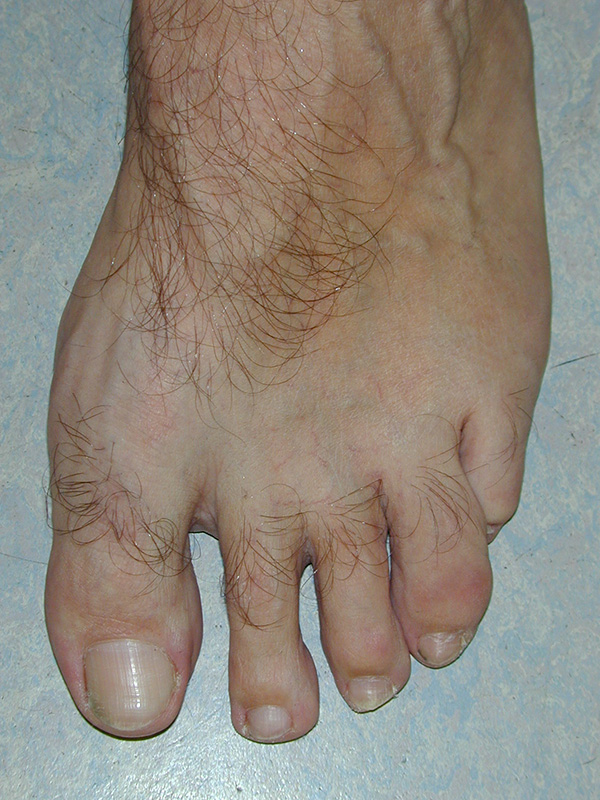

Vorfußbreite

Eine Verbreiterung des Vorfußes wird als Spreizfuß bezeichnet. Ursächlich ist meist eine Deviation des ersten Metatarsale nach medial und/oder eine Abweichung des fünften Metatarsale nach lateral. Die Abweichung kann im Röntgenbild quantifiziert werden. Der Winkel zwischen Os metatarsale I und II wird als pathologisch zu bezeichnet, wenn er in der belasteten dorsoplantaren Röntgenaufnahme 9° überscheitet. Der Intermetatarsalwinkel IV/V wird ab einem Wert von mehr als 8° als erhöht.

Abbildung 15: Schwere Spreizfußdeformität (M. Walther).

Abbildung 16: Belastetes dorsoplantares Röntgenbild des Fußes. Zur Beurteilung des Spreizfußes wird der Intermetatarsalwinkel I/II (grüne Linien - Norm < 9 Grad) und der Intermetatarsalwinkel IV/V (blaue Linien - Norm < 8°) bestimmt. Die Abweichung der Großzehe ist durch den Hallux valgus Winkel definiert (grüne/rote Linie), eine Fehlstellung innerhalb der Großzehe durch den Interphalangealwinkel (rote/gelbe Linie) (M. Walther).

Zum Lesen der Bildbeschreibung und zur Vollansicht bitte die Bilder anklicken.